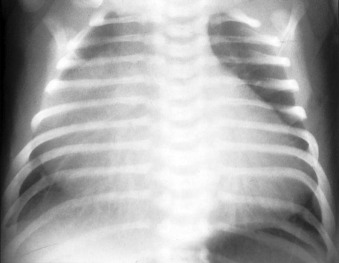

In this chest radiograph in an infant, there is gross cardiomegaly, particularly of the right-sided contours due to Ebstein’s anomalies.